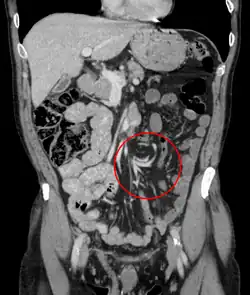

Coronal CT of the abdomen, demonstrating a volvulus as indicated by twisting of the bowel stock